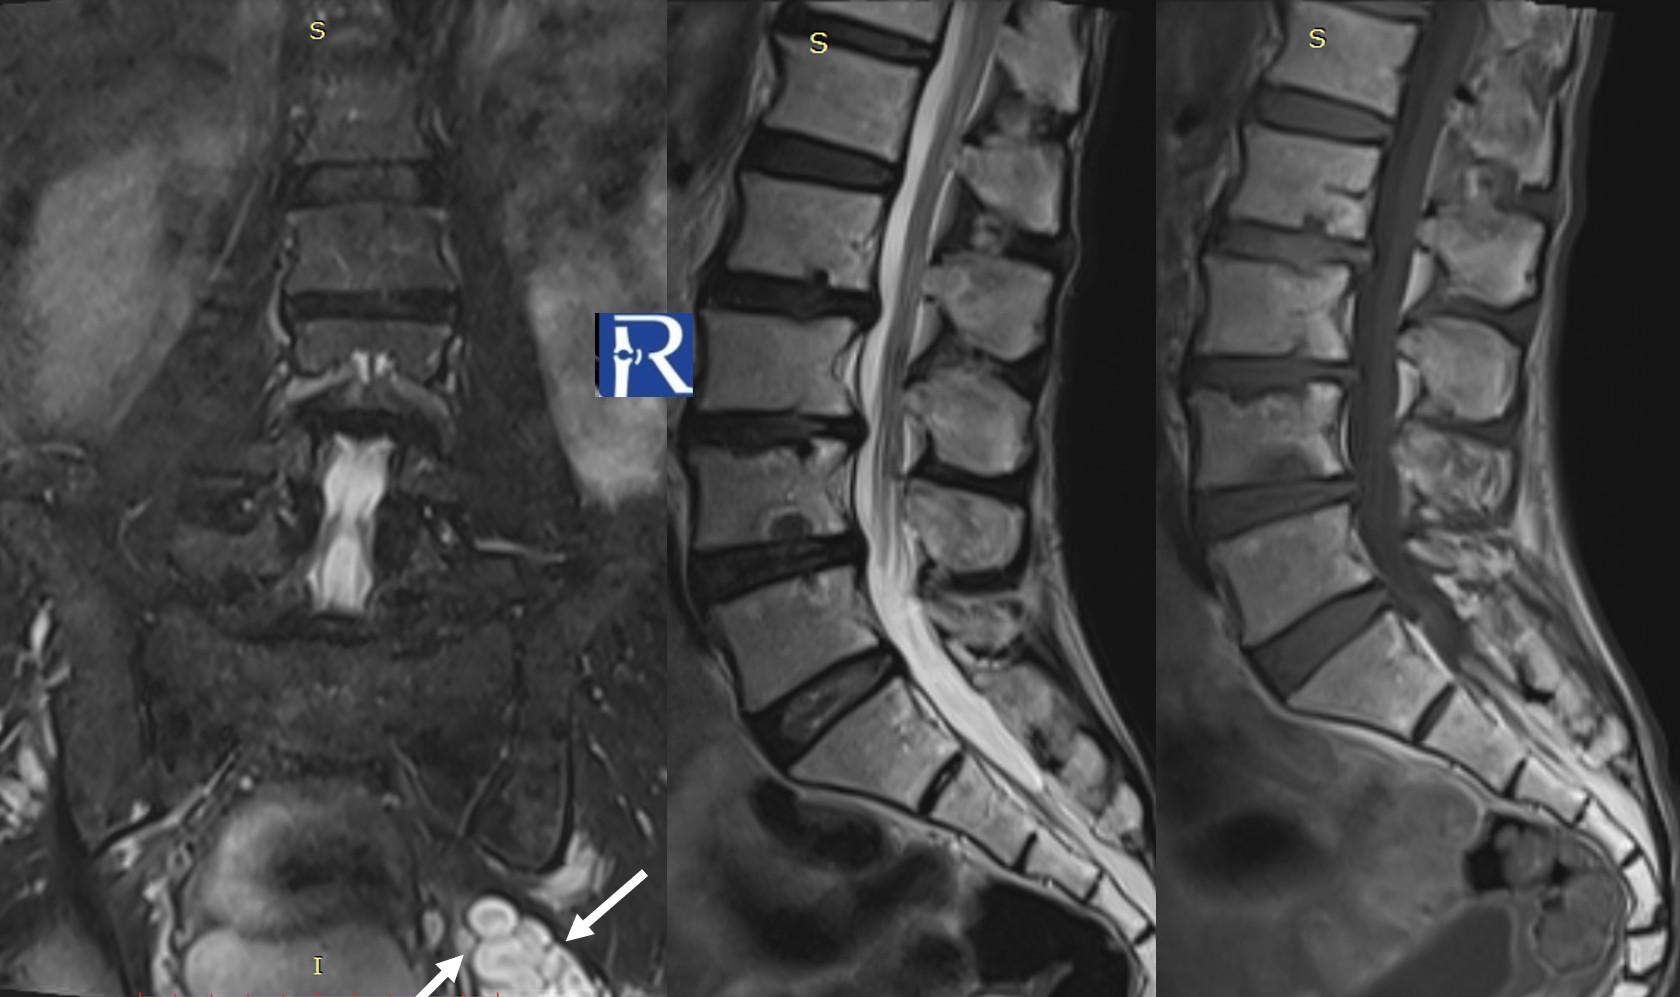

Clinical Background A 77-year-old patient with Ankylosing Spondylitis presented after a low-energy fall with acute thoracic pain. Imaging Findin ...